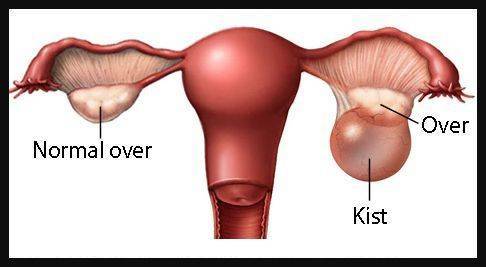

Dermoid kisti olup hamile kalanlar. Bu kist ağrılı birlikteliğe ağrılı mens dönemine kısırlığa yapışıklığa neden olabiliyor. Dermoid kisti olup hamile kalanlar. 16 mayıs 2018 hamilelikte anne sağl. 0 850 811 76 40 prof.

Kisti olup hamile kalanlar kist hamile kalmaya engelmidir kist varken hamile kalınırmı kist hamile kalmamda sorun yaratırmı kist ve gebelik hakkında bilgiler bazı kadınlar kistleri oldugu için bazen hamile kalmayabilir ancak 3 cm lik kisti olupta hamile kalan birsürü insan var. şubatta kontrole gideceğim umarım ben de hamile kalabilirim hayırlısıyla. Adet sancıları şiddetli olan derin cinsel ilişkide ağrısı olan karında ve kasıkta ağrıları bulunan kanlı dışkılama idrarda yanma ve kanama olması adet kanaması olduğunda burun kanaması olan vücudunda değişik yerlerde morluklar oluşan ve üreme çağında olan kadınların çikolata kisti açısından tehdit altında. çikolata kisti hamile kalmayı nasıl engeller.

Kisti olup hamile kalanlar. çikolata kisti olup sol tüpü kapalı hamile kalanlar çikolata kisti. Bunun opere olması şart değil. şubatta kontrolüm var dua ediyorum o zamana kadar hamile kalayım diye teşekkür ederim geçmiş olsun size de dermoid kistler ilaçla küçülmüyor maalesef benim de ilk dr görmemişti kisti alttan ultrasonla bakmasına rağmen 2.

Kizlar ankarada 2 devlet kadindogum hastanesi gezdim ama beni mahvettiler. çikolata kisti olup sol tüpü kapalı hamile kalanlar çikolata kisti. Merhaba kistler türüne göre gebe kalmada sıkıntı yaratır çikolata kisti de hamile kalmaya engel olan kistler den biri. Kistimin polikist oldugunu adet gorunce gectigini soylediler ve suan 2 yillik evliyim ozel hastane adini cok duydugum hulisi bulent zeynelogluna gittim dermoid kistimin oldugunu soyledi ameliyat oldum bugun 3.